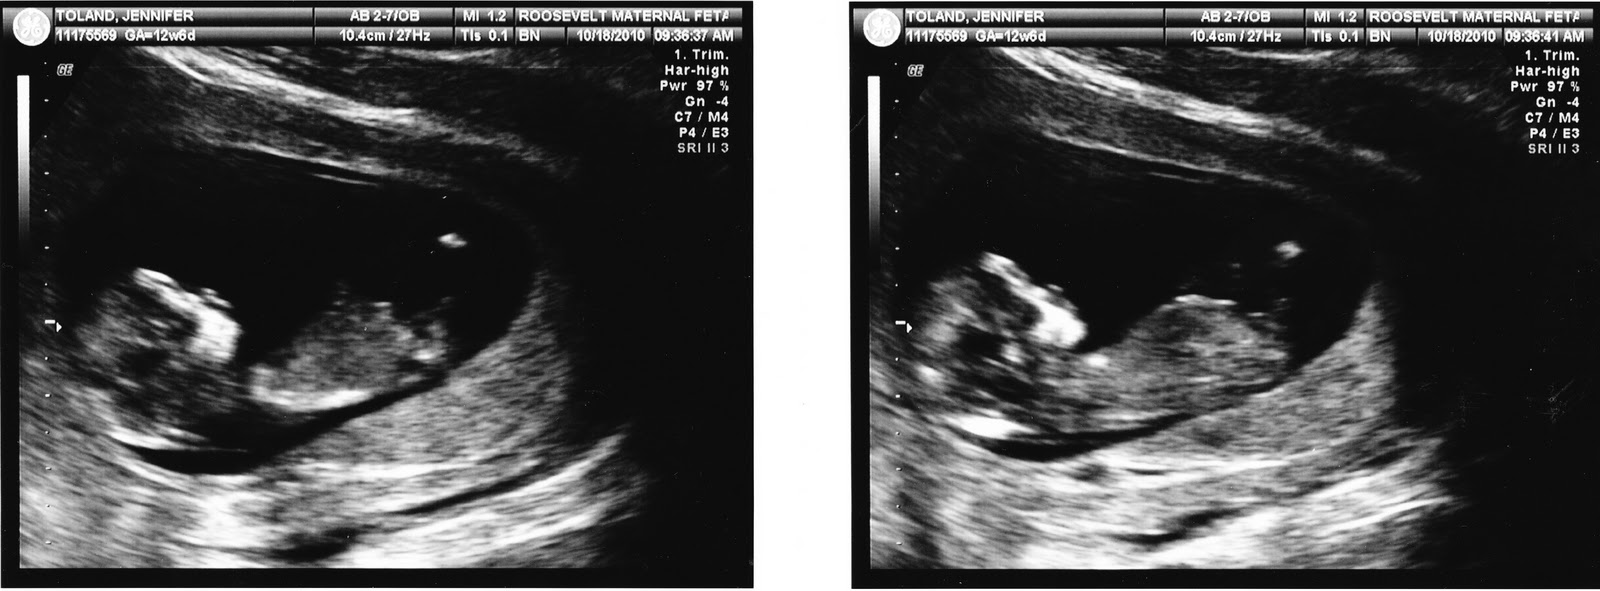

Our first ultrasound courtesy of St. Luke’s Roosevelt Hospital…and this little one’s first close up. 2 1/2 inches and the size of a large plum. He/She obviously takes after Rick in loving the camera…but we both agree, that nose is all Toland!

Such a happy visit.